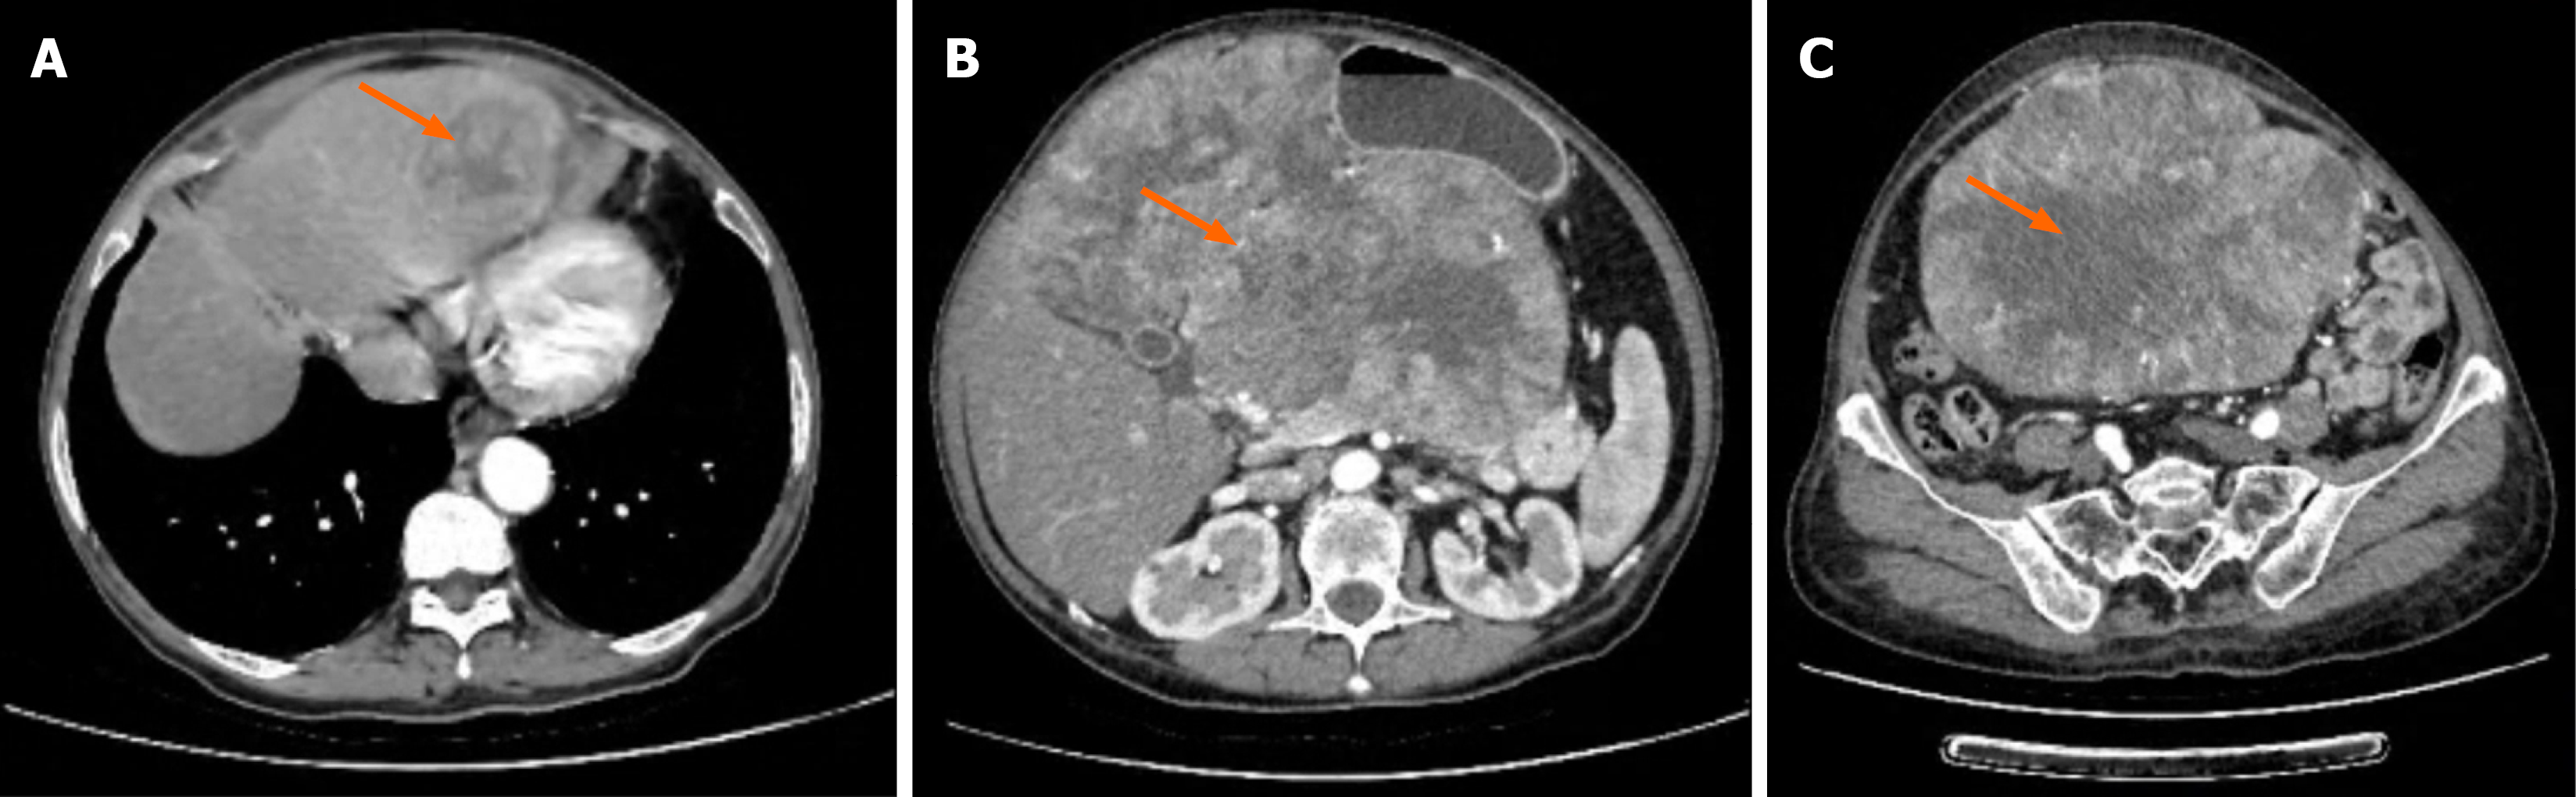

Preoperative contrast-enhanced computed tomography on March 29, 2024 demonstrated a 14.1 cm × 18.6 cm × 26.8 cm heterogeneous mass occupying the hepatogastric space, with patchy low-density areas and extension toward the pelvis. A 4.4 cm × 3.9 cm lesion consistent with hepatic metastasis was identified in the left liver lobe, showing uneven en

On April 9, 2024, the patient underwent open exploratory laparotomy. Intraoperative exploration confirmed a 14.1 cm × 18.6 cm × 26.8 cm mass originating from the gastric greater curvature near the pylorus, extending posteriorly into the retroperitoneal space and invading the pancreatic body and tail, which appeared atrophic. A 4.4 cm × 3.9 cm metastatic lesion was identified in the left liver lobe, and there was no evidence of peritoneal seeding or distant extra-abdominal metastases.

Preoperative differentiation between gastric-origin LMS and retroperitoneal sarcoma can be difficult, as both may appear as large heterogeneous masses with poorly defined boundaries on imaging. In our patient, the loss of fat planes between the mass, pancreas, and liver led to the initial misdiagnosis of retroperitoneal sarcoma. Intraoperative findings confirming a gastric origin near the pylorus highlight the importance of comprehensive exploration and intraoperative pathological assessment.